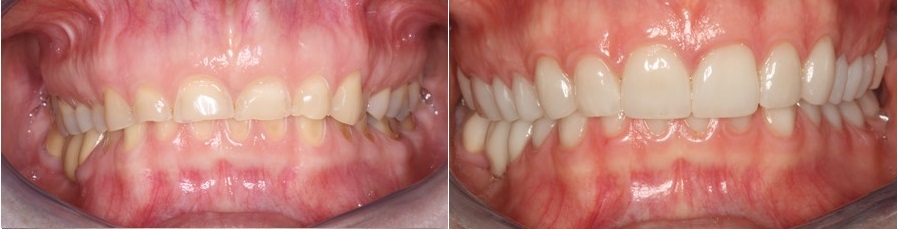

Στην εικόνα που ακολουθεί βλέπουμε τα επιπεδωμένα δόντια, και την απώλεια του σχήματος τους που είναι εμφανή τόσο στο χαμόγελο όσο και στην ενδοστοματική εικόνα δεξιά.

Στην φωτογραφία που ακολουθεί βλέπουμε την εικόνα των δοντιών της ασθενούς πριν και μετά την συγκόλληση των όψεων ρητίνης και πορσελάνης στα πρόσθια δόντια και των επένθετων πορσελάνης στα οπίσθια δόντια της άνω γνάθου.

Διάβρωση δοντιών- θεραπεία

Η εργασία γίνεται σταδιακά και όταν ολοκληρωθεί, όλα τα δόντια έχουν αποκατασταθεί στο νέο ύψος του προσώπου με ολοκεραμικές εργασίες οι οποίες αποδίδουν την μασητική μορφολογία, διορθώνουν όμως παράλληλα και μικρά αισθητικά προβλήματα στο χαμόγελο που είχε η ασθενής.

Το χαμόγελο της ασθενούς πριν και μετά την αποκατάστασηΔιάβρωση δοντιών- θεραπεία

Η εικόνα των δοντιών πριν και μετά την αποκατάσταση